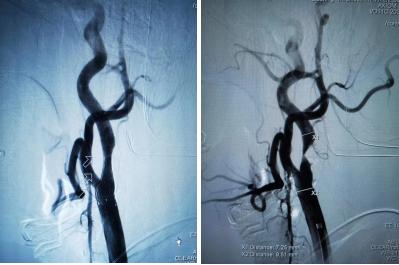

近日,沈阳市苏家屯区中医医院成功开展了辽宁省首例"心脑联合支架"手术。患者因突发左侧肢体无力,以急性脑梗死入院。脑血管造影右颈内动脉95%重度狭窄,住院期间心绞痛发作,冠脉造影右冠状动脉90%狭窄。经神经内外科、神经介入、心内科联合会诊与协作,同台完成心脑联合支架,术后患者病情稳定,健康出院。